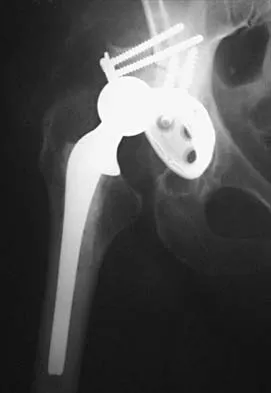

A 42-year-old man sustained the periprosthetic fracture shown in Figures 19a and 19b. The femoral component is well fixed. What is the next most appropriate step in management?

Explanation

The patient has a periprosthetic fracture below the femoral stem. The component is porous coated and well fixed. Open reduction and internal fixation, leaving the stem in place, can be performed when bone quality is good. Plating with or without allograft struts and supplemental cerclage fixation generally is acceptable. If the component is loose, revision to a longer device is recommended with appropriate stabilization of the fracture using the aforementioned methods. If bone loss has occurred, allograft supplementation or a tumor prosthesis may be indicated. Fractures located well below the stem tip can be treated without regard for the prosthesis. Closed reduction and bracing is not associated with good results for periprosthetic femoral fractures. Retrograde intramedullary nailing is not appropriate for this fracture. Duncan CP, Masri BA: Fractures of the femur after hip replacement. Instr Course Lect 1995;44:293-304.